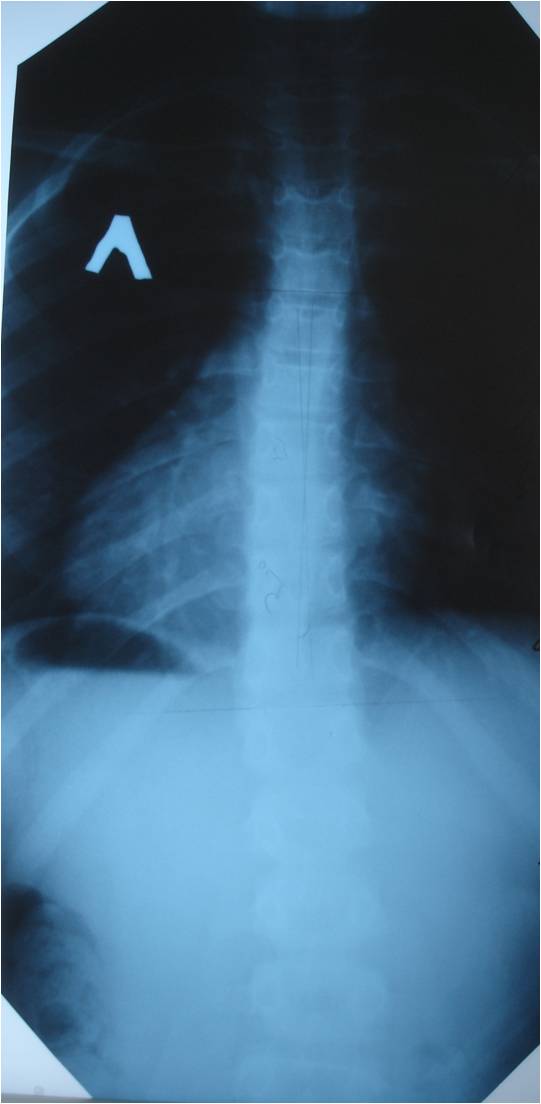

А в анамнезе что ? Контактные площадки 7-го позвонка уплотнены , сам он немного уменьшен по высоте и небольшая клиновидная его деформация - на 1 степ старого компрессионного похоже . И 1 степ сколиоза .

Контактные площадки 7-го позвонка уплотнены , сам он немного уменьшен по высоте и небольшая клиновидная его деформация - на 1 степ старого компрессионного похоже .

На основании болей, возраста, снижения высоты тела только одного позвонка можно предположить остеохондропатию тела 8-го грудного позвонка – болезнь Кальве.

На Кальве не тянет. Костная структура позвонка не изменена. Это может быть проекционное искожение. T8 находится как раз на вершине сколиотической дуги.

На Кальве не тянет. Костная структура позвонка не изменена. Это может быть проекционное искажение. T8 находится как раз на вершине сколиотической дуги.

Вот именно этот-то позвонок меня и смущает. Болевой синдром не свойственен собственно сколиозу, нужны другие причины. Да и сколиозик-то небольшой, на грани нарушения осанки.

Трапецевидную форму тел позвонков на уроне Th6-Th8-можно рассматривать как вариант нормы(из лекций профессора Жаркова П.Л.).

На снимке, уважаемый Александр (простите, отчество не знаю), не клиновидная, а трапециевидная деформация позвонка? Хорошо, допустим, норма. Но наличие болевых ощущений в области позвонка измененной формы не должно ли вызвать некоторую настороженность?

Похоже на клиновидную деформацию Тн-8 (снижение высоты в переднем отделе тела позвонка ) -компресия.

Посттравматическая деформация D8 в исходе его компрессионного перелома?